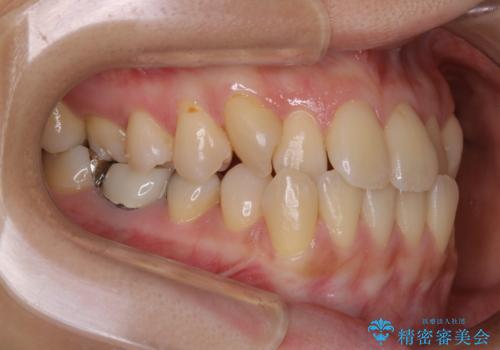

前歯が内側に入っている:インビザライン治療

- 上の前歯は内側に入っていることが気になりご相談にいらした方です。インビザラインにて治療を行いました。

1週間でのマウスピース交換を指示していましたが、20時間以上使えない時があると不安との事で、2週間ごとの交換にしていました(実際はほとんど20時間以上使用できていたようです)。治療終了まで時間はかかりましたが、最終的に綺麗に並べることができ、大変喜んでいただけました。